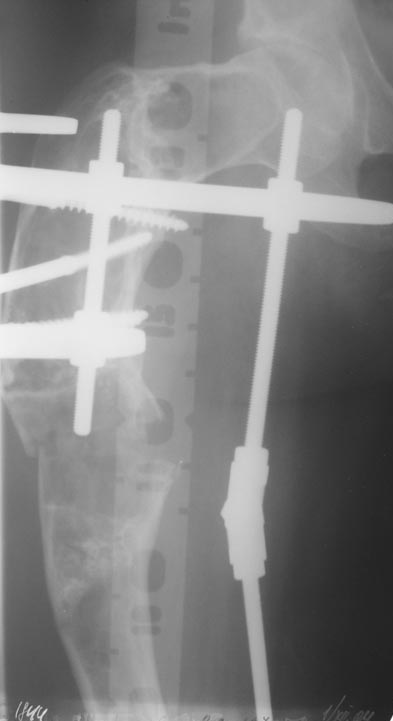

Leonid Pollyak 27 Ноябрь 2004, 11:17

Уважаемые коллеги! Большое спасибо за живой отклик и предложения по тактике лечения. Больной произведен первый этап - стержневой аппарат издвух баз, кортикотомия, остеоклазия и начата коррекция в аппарате. Почти исправлен угол, не сегодня укорочение 2см. Когда завершим коррекция, представлю рентгенограммы.

В ноябре этого года я обращался с просьбой о помощи в выборе тактики лечения больной с деформацией бедра на почве фиброзной дисплазии. Были получены интересные и очень полезные советы по операции.

Хотелось бы показать, что получилось в результате.

Операция выполнялась с помощью А.Н.Челнокова. Очень понравилась технология выполнения блокируемого остеосинтеза с использованием спицевого дистрактора, модифицированный гвоздь с латерализованным проксимальным отделом и возможностью многовинтовой фиксации проксимального и дистального участков бедра.